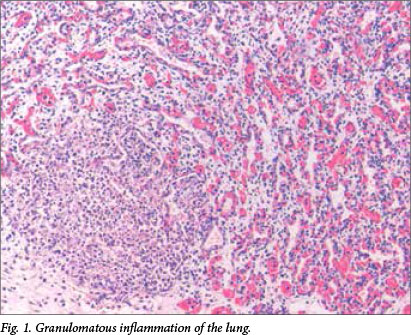

Microscopic examination revealed multiple well-formed granulomas in both lungs (Fig. 1), kidneys, the liver (Fig. 2), brain (Fig. 3) and right adrenal gland. Fungal elements consistent with Candida spp. were seen within these granulomas. The periodic acid-Schiff special stain highlighted the fungal organisms (Fig. 4). Examination of the autolytic tissue from the brain showed an extensive fungal meningoencephalitis (Fig. 3). Examination ofthe thymus revealed parenchymal haemorrhages seen in the first 12 hours following a stressful event. Marked sinusoidal congestion was present in the spleen.